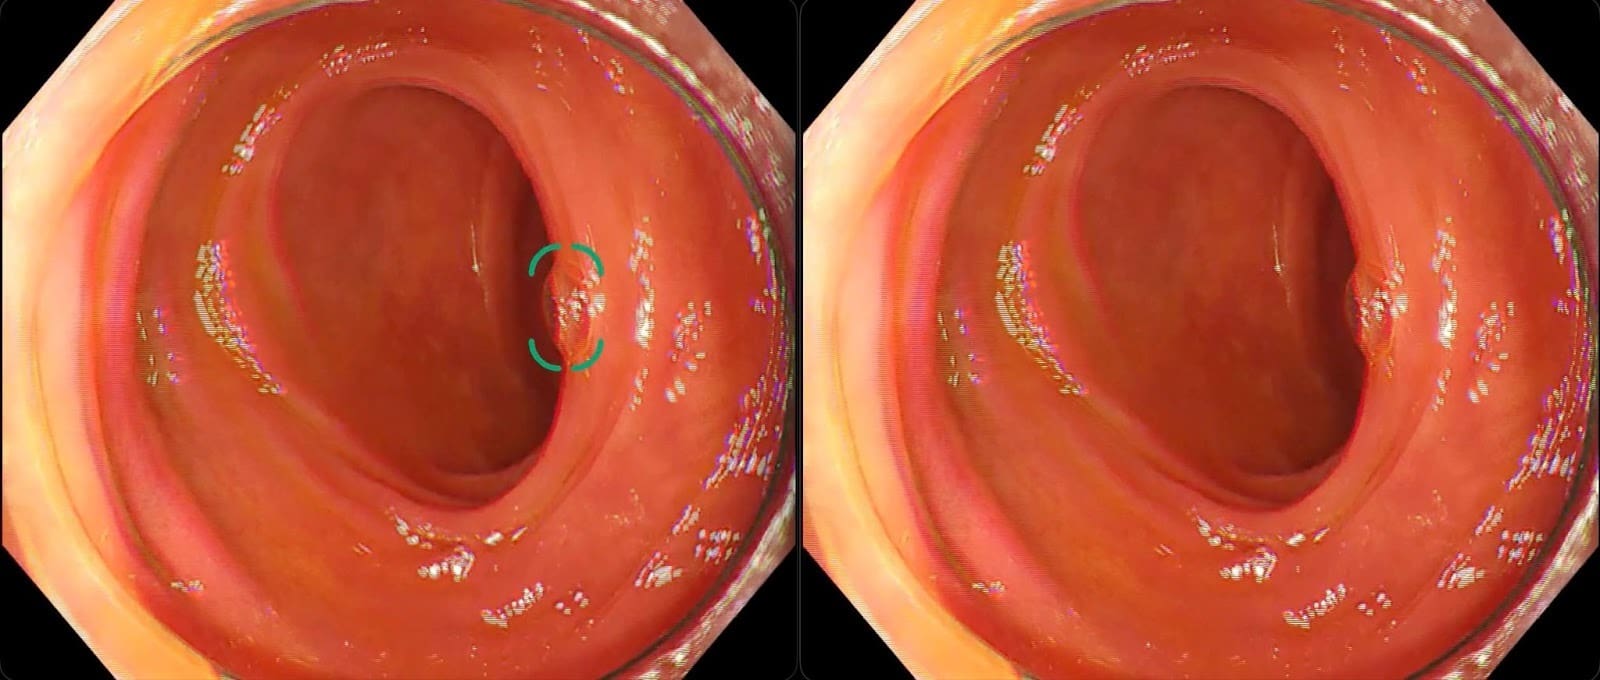

大腸ポリープ候補を検出し大腸内視鏡検査を支援する「EIRL Colon Polyp」、検出精度を改善した新モデルを発売 - エルピクセル株式会社